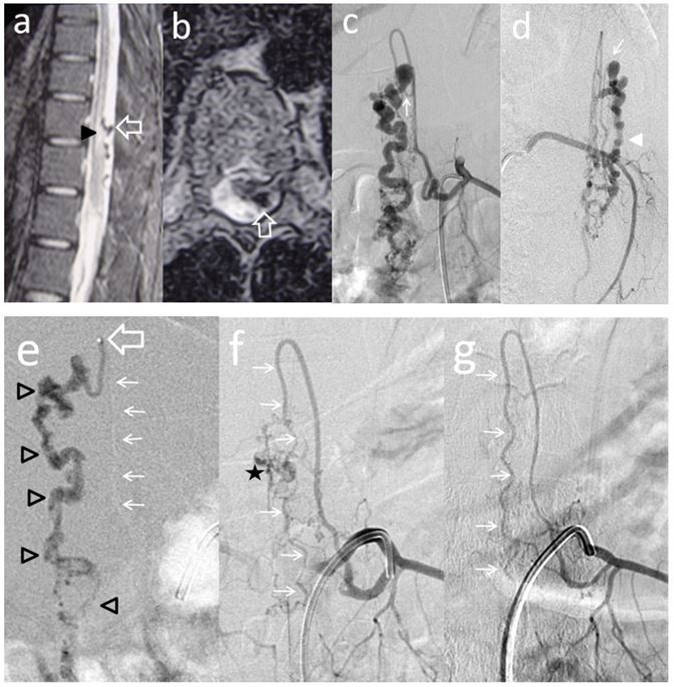

Figure 3.Case # 3: a) T2W MR sagittal and b) axial non contrast spinal MRI, showing flow voids in the dorsal aspect of conus and epiconus (open arrows) with hypersignal extending towards the lower dorsal spinal cord (arrowhead in a). c and d) Segmental left T11 angiogram in AP and lateral projections. The artery branches off to an enlarged ASA (Artery of Adamkiewicz) and also a thinner PSA feeding the PMAVF. The fistula is located posterolaterally (thin arrow in c) and d), draining downwards (arrowhead). e) Injection of 33% n-BCA with rapid microcatheter removal. See the tip of the microcatheter in the curve of the PSA (open arrow). The glue reached the fistulous site and the draining vein (open arrowheads) f) Left T11 angiogram following embolization did not show any shunt and only remnants of the abnormal draining veins were seen (star) with preservation of the ASA axis (thin arrows). g) An angiogram performed 3 months postembolization demonstrated complete eradication of the AVF and preservation of the artery of Adamkiewicz (thin arrows).

Two out of 4 patients were diagnosed and studied preoperatively with both spinal MRI and CT scans, 1 patient with MRI and the other patient with CT/CT Angiography with 3D reconstruction. Large and tortuous flow voids with large to giant venous pouches or pseudoaneurysms (3 of our cases - type c) causing compression of the spinal cord were found lying ventrally and, in another one, posterolaterally to the spinal cord. Hyperintensity in T2W sequences in the spinal cord was noted in all of them. There were no cases where a hemorrhage was exhibited. The angiographic studies confirmed the 4 large or giant pouches at the draining vein fed by ASA and or PSA and ascending (2 cases), descending (1 case) or metameric (1 case) venous drainage. The blood flow was moderate in 1 case and very fast in the other 3 patients (see Table 2 and Figure 1, Figure 2, Figure 3, Figure 4).

We used transarterial approach and a single session achieving complete obliteration of the fistulae while preserving the normal vasculature, mainly the ASA, in all of our 4 cases using either different concentrations of n-bca alone tailored to the blood flow velocity (cases 1,2 and 3), or a combination of coils and onyx 18 (case 4). In this last case, the high flow fistula and the presence of a giant pseudoaneurysm at the venous varix compressing the spinal cord prompted us to deploy coils in the sac and in the draining vein to slow down the blood flow and decrease the chance of distal embolism. To date, we do not have Onyx of higher concentration than Onyx18 available in our country. In high flow macrofistulae, our strategy to slow down the flow to allow casting of the polymerizing embolic mixture in the fistulous site avoiding distal embolism includes lowering mean arterial pressure down to 60-70 mm Hg pharmacologically, by embolizing with concentrations of 66% of n-bca in lipiodol, as well as the placement of detachable coils in the event of very high flow with pseudoaneurysms at or very close to the fistulous site as a first step, to trap the liquid embolic material injected as second step (see Figure 1, Figure 2, Figure 3, Figure 4).